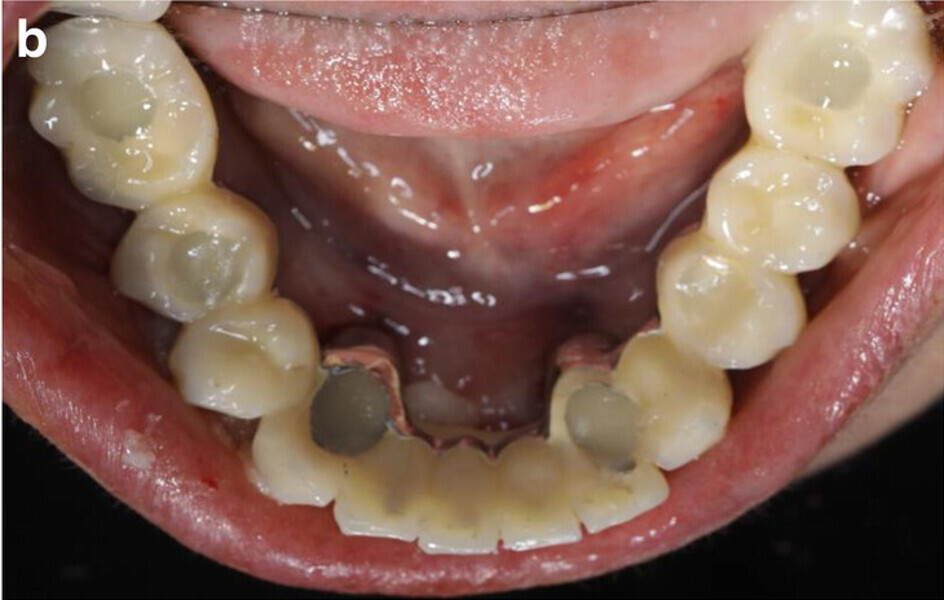

Fig. 3a: Frontal (a) and occlusal view (b) of the study models after extraction of teeth #41, 31 and 32.

Fig. 3b: Frontal (a) and occlusal view (b) of the study models after extraction of teeth #41, 31 and 32.